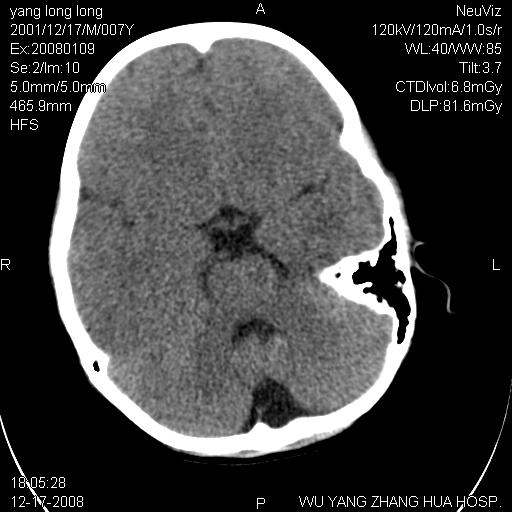

标题: PED1686:M7Y,头外伤,家人及自诉平时无任何不适。 [打印本页]

标题: PED1686:M7Y,头外伤,家人及自诉平时无任何不适。

考虑蛛网膜囊肿,请老师们看看多指导指导。

多考虑大枕大池。本例颅骨歪歪的,灶后枕骨似有膨胀征像(为蛛网膜囊肿征像),但整个左侧枕叶后方枕骨均有向后膨隆,所以暂不考虑蛛网膜囊肿。必要时随访

鉴别巨大枕大池与蛛网膜囊肿之间,倾向前者。

枕大池蛛网膜囊肿

蛛网膜囊肿可能性大

考虑枕大池蛛网膜囊肿

考虑枕大池蛛网膜囊肿。建议必要时mri检查。

病变向两侧延伸,颅骨内板受压侵蚀,似有张力!!还是考虑蛛网膜囊肿!!